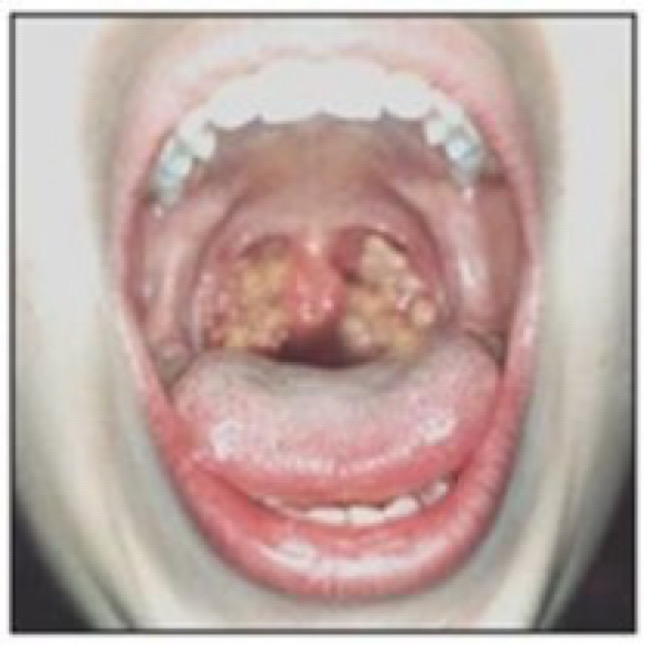

디프테리아는 심각한 박테리아 감염 중 한 가지로 코의 점막, 목과 피부에 영향을 미치는 전염병으로 알려져 있다.

잠복기는 대체로 2일에서 6일 정도 가량이며 디프테리아에 걸리면 목에 심한 통증을 느끼며 기침을 하게 된다. 또한 목이 쉬고 목소리가 변하며 호흡 곤란, 콧물 점도가 나타난다.

발열과 오한 또한 나타나며 제때 치료를 받지 않는다면 심장과 호흡기, 신경에 후유증이 크게 남을 수 있기 때문에 적절하고 빠른 치료가 필요하다.